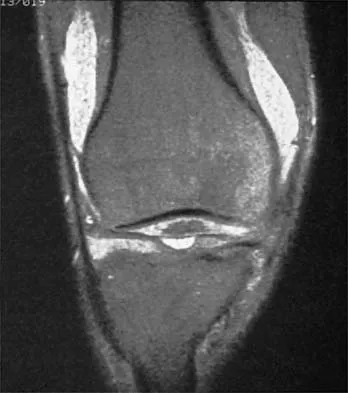

A 50-year-old moderately active female feels a 'pop' in her posterior knee while squatting. An MRI is obtained as seen in the figure.

It demonstrates a medial meniscus posterior root tear with 4 mm of extrusion and minimal osteoarthritis. What is the most appropriate surgical management?

Explanation